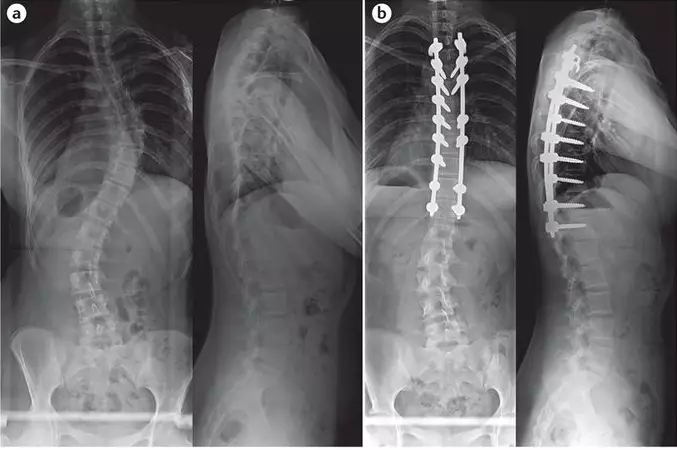

Сколиозата представлява триизмерна деформация на гръбначния стълб. 3 на всеки 100 деца са получили диагноза сколиоза. Това е тихо състояние, което идва в живота Ви и се настанява там за цял живот. Обикновено поразява деца на възраст между 9  и 16 години! 85 % от тях са момичета!

За щастие при повечето деца ежедневната лечебна гимнастика и корсетите, които се налага да носят ежедневно минимум 18 часа дават резултат. Но на 300 българчета годишно се налага оперативна намеса, за да се преборят със сколиозата.

Операцията от сколиоза е възможно най-тежката, която може да се случи в ранна детска възраст! Но нашите деца са герои и ние от Фондация „Живот със сколиоза“ искаме да ги подкрепим в този най-труден за тях момент.